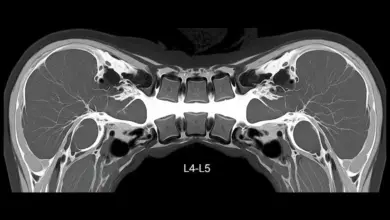

Muitas vezes, uma dor na coluna pode indicar outras condições ortopédicas, como por exemplo, uma hérnia de disco.